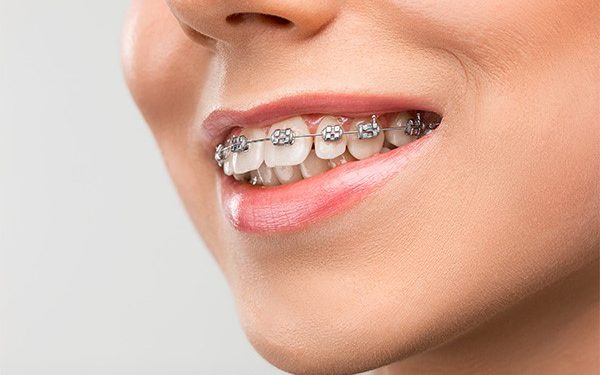

ارتودنسی دندان یکی از خدمات دندانپزشکی است که تأثیر بسزایی در زیبایی لبخند میگذارد. امروزه خدمات دندانپزشکی فراتر از یک دندان کشیدن ساده و درمانهای معمول است. در حال حاضر با پیشرفت فناوریهای حوزه پزشکی و خصوصا دندانپزشکی، درمانها و خدمات دندانپزشکی هم بسیار متنوعتر شده و بخش عمدهای از این درمانها را خدمات زیبایی دندان تشکیل میدهد.

گزینههای درمان ارتودنسی برای بزرگسالان ممکن است شامل بریسهای سنتی، ترازهای شفاف یا سایر وسایل تخصصی باشد. نوع درمان توصیه شده به مشکل خاص ارتودنسی و ترجیحات و اهداف شخصی فرد بستگی دارد.

ارتودنسی یک تخصص دندانپزشکی است که بر اصلاح نامرتبی دندانها و فکها تمرکز دارد. درمان در هر سنی میتواند موثر باشد، اما سن ایدهآل برای کودکان معمولا بین 10 تا 14 سال است. مشکلات ارتودنسی قابل اصلاح شامل دندانهای کج یا نامرتب، اوربایت یا آندربایت، شلوغی دندانها، مشکلات فاصله گذاری و مشکلات بایت است. گزینههای درمانی ممکن است شامل بریسهای سنتی، ترازهای شفاف یا سایر وسایل تخصصی باشد. با این حال، همه افراد واجد شرایط درمان ارتودنسی نیستند و عواملی مانند بهداشت نامناسب دهان، بیماری لثه، ناهماهنگی شدید فک، شرایط خاص پزشکی یا ترمیمهای دندانی گسترده ممکن است باعث شود که فرد واجد شرایط نباشد.